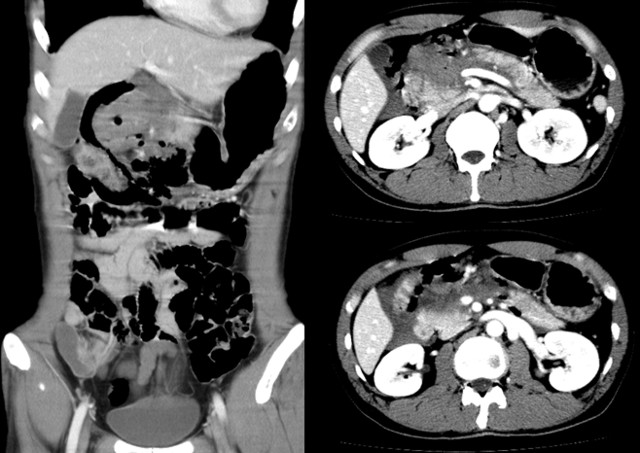

A 36-year-old male was referred to the emergency room for severe abdominal pain developing several hours after being assaulted. On admission, his vital signs were stable but he complained of severe abdominal pain. On physical examination, he had bruises on the face due to physical abuse, and tenderness with rebound tenderness was observed in the epigastric area. Laboratory results on admission revealed a hemoglobin level of 15.6 g/dL (reference range: 13.5-17.5 g/dL), white blood cell count of 16,600 µL-1 (reference range: 4,500-11,000 µL-1), and platelet count of 153,000 µL-1 (reference range: 150,000-440,000 µL-1). The aspartate aminotransferase (AST) and alanine aminotransferase (ALT) levels were increased up to 104 IU/L (reference range: 10-44 IU/L) and 131 IU/L (reference range: 10-44 IU/L), respectively. The serum amylase and lipase levels were 398 IU/L (reference range: 28-100 IU/L) and 937 IU/L (reference range: 0-60 IU/L), respectively. Abdominal computed tomography (CT) demonstrated free intraperitoneal air around the duodenum suggesting duodenal injury. Complete transection of the pancreas with a large contained hematoma around the neck of the pancreas was noted, which was consistent with grade IV pancreatic injury scale according to the American Association for the Surgery of Trauma [8] (Figure 1).

Figure 1. Abdominal CT scan demonstrates free intraperitoneal air around the first portion of the duodenum and transection of the main pancreatic duct at the neck of the pancreas with hematoma. |